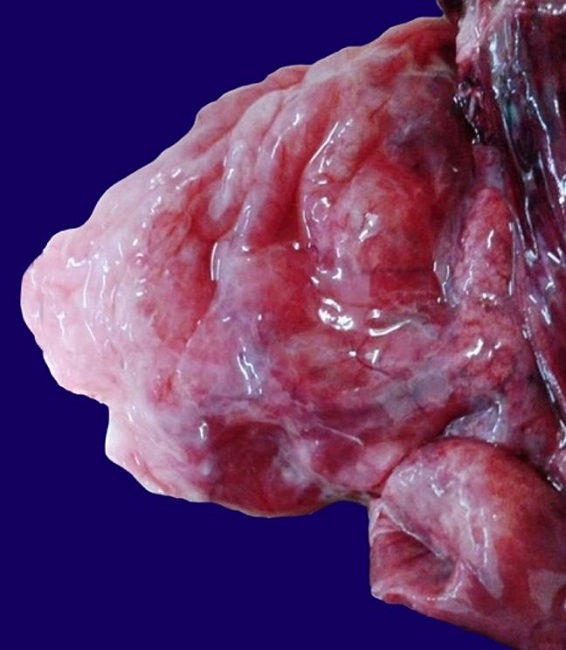

On opening the chest, a mediastinal shift to the left hemithorax was noted. The heart and lungs together weighed 38 grams. The right lung measured 9 cm × 7 cm × 3 cm and showed a hyperinflated aspect exhibiting multiple cystic formations with up to 7 cm in diameter ( Figure 1 ). The left lung measured 4 cm × 2cm × 1 cm and appeared immature. The heart had normal anatomical connection with the large arteries, but on opening, a 2 mm atrial septal defect was evident. No other systemic malformation was present.